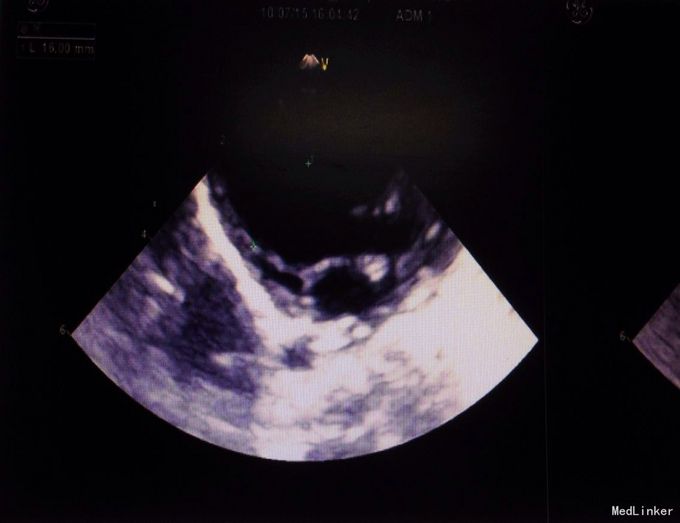

体检:生命体征正常,全身皮肤黏膜无黄染,腹隆,肝脾肋下未及,宫高29,腹围88, FHR148,头位,未触及宫缩,未行内诊,骨盆外测量22-26-18-8 辅助检查:2周前外院检测总胆汁酸25umol/L,一周前复查总胆汁酸60umol/L,今日外 院B超示晚孕,单活胎,头位,胎儿房间隔中部囊样无回声,考虑膨胀瘤可能,本院检查 结果如下图

入院诊断:孕39周待产,G2P1,ICP 诊疗经过:患者入院后给予护肝等对症支持治疗,顺娩1活女婴,分娩后子宫收缩好,新 生儿心脏彩超示动脉导管未闭,拟随访。